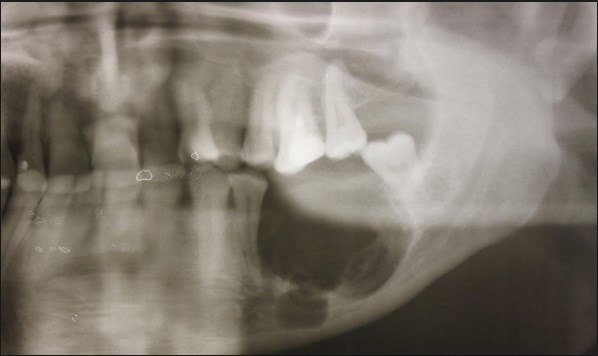

Рентгеновские снимки посттравматического остеомиелита челюсти: Медицинские случаи

Раздел: Образы вокруг